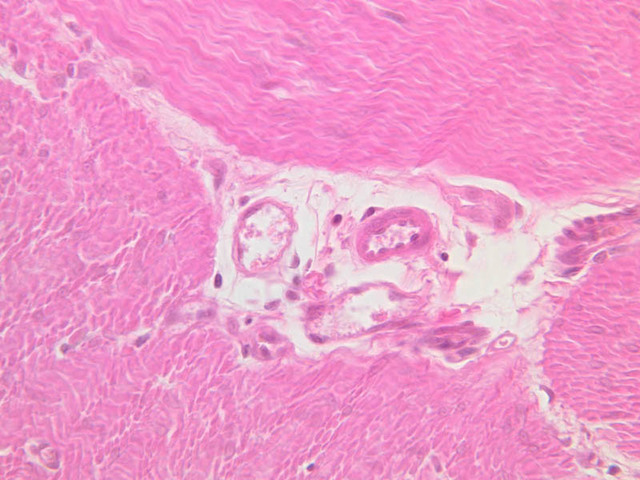

Blood passes from the elastic arteries via arteries of intermediate type into the muscular (distribution) arteries. Locate and examine a muscular artery in slide A-28 (Renal artery & vein, H&E [2.5x, 10x-labeled, 20x, 40x-labeled] [10x-labeled, 20x, 40x]; AF [10x-labeled, 20x, 40x]). Note that the tunica intima is separated from the tunica media by a thick internal elastic membrane which has a scalloped appearance. The tunica media consists of many layers of smooth muscle cells arranged concentrically in a spiral fashion (A-28, H&E [2.5x, 10x-labeled, 20x, 40x] [2.5x, 10x, 20x, 40x, 40x] [2.5x, 10x, 20x]). An external elastic membrane is present, but is thinner and less complete than the internal elastic membrane. The tunica adventitia is about equal in size to the media in this vessel and is more intensely eosinophilic in its staining properties. Note the appearance of small blood vessels in the outer part of the tunica adventitia. You may also be able to see occasional nerve fibers.